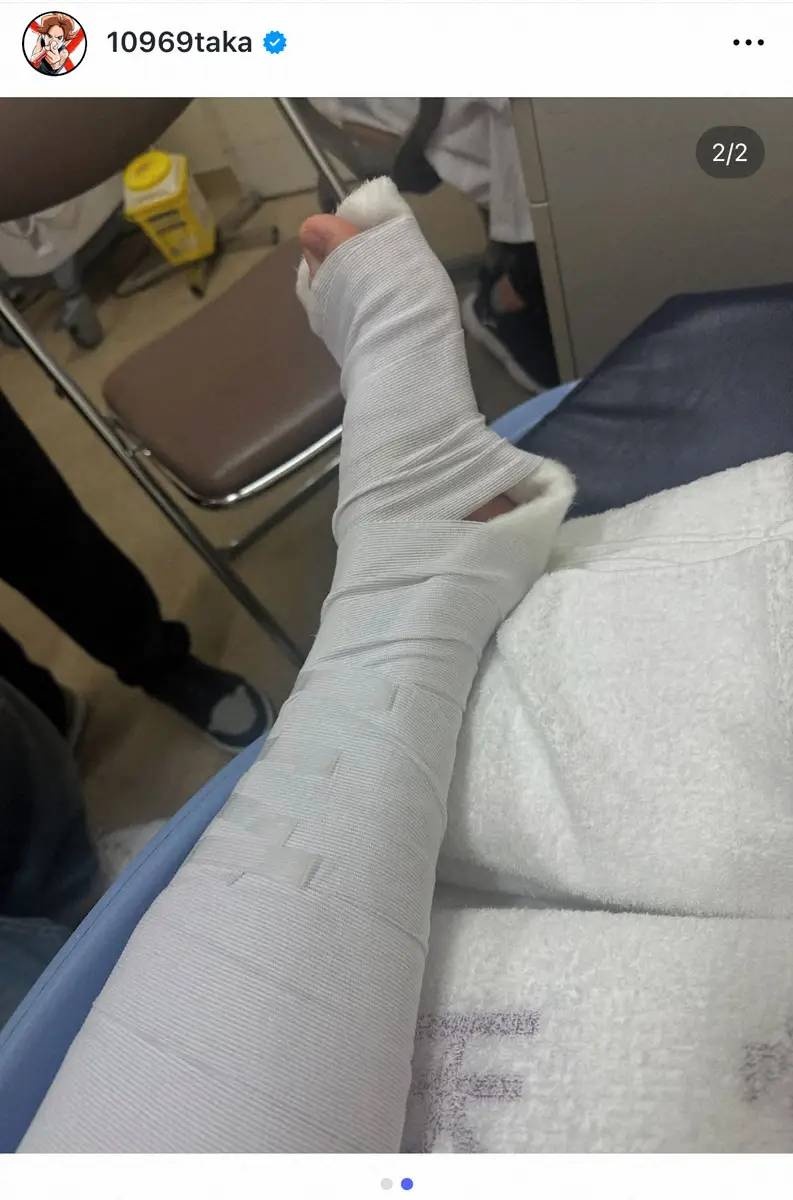

ロックバンド「ONE OK ROCK」のTaka(37)がライブ中に左足を骨折したことを1日、自身のインスタグラムで明かした。

また「でも骨折してました」と左足がギプスで固定されたショットを投稿し「あとでインスタライブしまーす」と伝えた。

その後のインスタライブで「人生初の公演中に足を骨折しました」と歌唱中に足を着いた際に「もの凄い勢いでぐちゃってなった」と左足小指の付け根を負傷したことを告白。ライブ後、すぐに病院へ行き骨折と診断された。